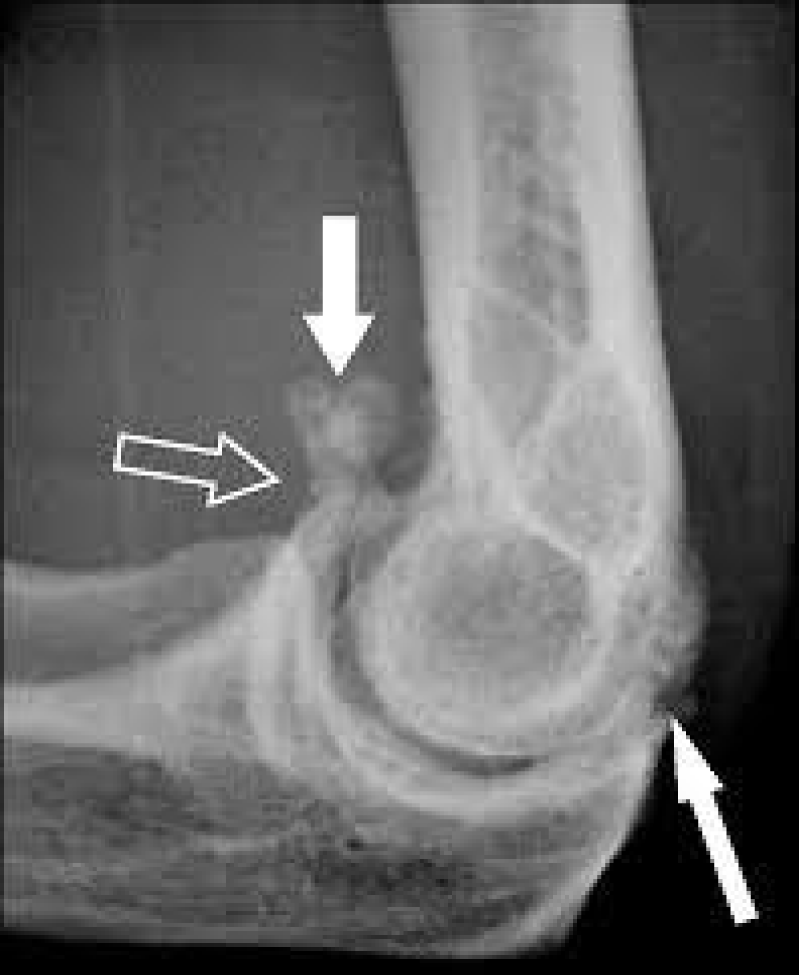

Loose Body in the Elbow Joint-This may be secondary to trauma, but frequently, the onset is insidious. The patient states that they suddenly developed a loss of either flexion or extension at the elbow. On passive joint testing, the clinician will probably elicit a springy end feel on either flexion or extension with a 10-15-degree loss of motion. Sometimes the loose body also blocks pronation or supination. It depends on precisely where the loose body is within the joint. Figure 5 is a sagittal CT scan of an interesting and unusual situation where loose bodies are located both anteriorly and posteriorly. It is likely that in this case both flexion and extension would be limited. This would present a challenge. This CT scan was selected for this article to illustrate potential locations for a loose body.

Download Image

Figure 5: Loose bodies in the elbow.